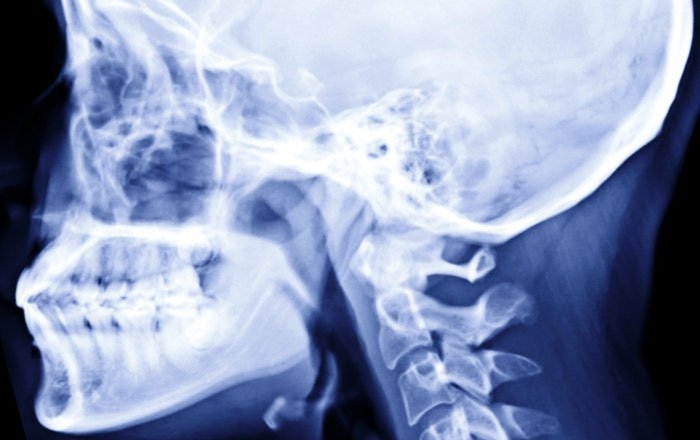

顎の骨格の成長発育については、矯正用のレントゲン写真が参考になります。

セファログラム(頭部X線規格写真)と呼ばれる矯正治療でよく使われるレントゲンは、毎回同じ規格で撮影できるため、骨格の経年変化を精密に比較することが可能です。

1年程度の間隔をあけて撮影した写真を比較し、骨の大きさや形にほとんど変化がなければ、顎の成長は終わったと判断します。